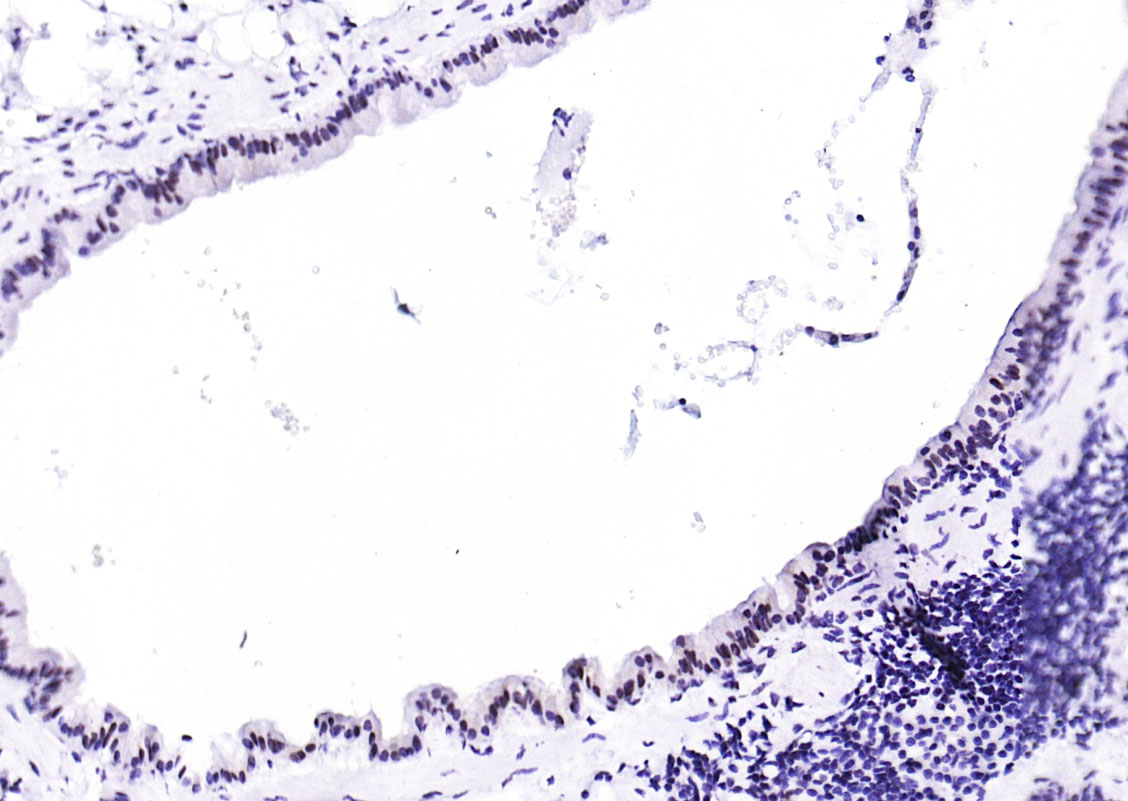

| 产品应用 | WB=1:500-1000, IHC-P=1:50-200, IHC-F=1:50-200, IF=1:50-200 Not yet tested in other applications. |

| {IHC-P} | {1:50-200} |

| {IHC-F} | {1:50-200} |